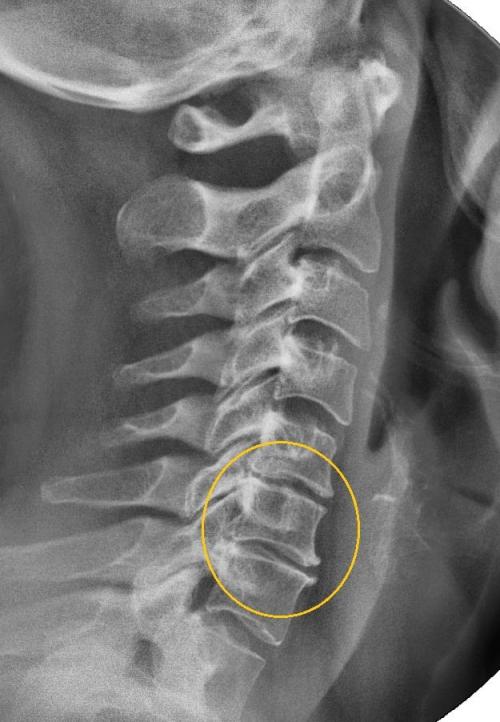

Хруст в плече, как лечить. Шейный остеохондроз

Щелчки и боль при вращении плеча — один из симптомов шейного остеохондроза 2 или 3 степени тяжести. Для патологии характерно постепенное разрушение вначале хрящевых межпозвонковых дисков, а затем костных позвонков. Причинами развития патологии становятся серьезные физические статические и динамические нагрузки, эндокринные заболевания (тиреотоксикоз, сахарный диабет), травмы, естественное старение организма. От остеохондроза часто страдают люди, проводящие много времени за компьютером, печатной машинкой, микроскопом. Для патологии характерна выраженная и разнообразная симптоматика:

Диагноз на рентгене.

Появление щелчков в плече связано с деструкцией позвонков. Они уплощаются, разрастаются. Организм пытается стабилизировать позвонки, предупредить их смещение с помощью формирования остеофитов. Они, в свою очередь, сдавливают чувствительные окончания, провоцируя спазмы скелетной мускулатуры. Это снижает функциональную активность плечевого сустава, приводит к нарушению кровообращения и уменьшению выработки синовиальной жидкости.